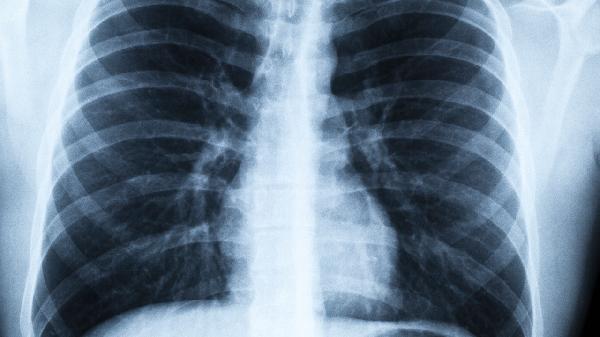

如何知道你的肺好不好?不妨看看这些特征,你是否“达标”!

想知道你的肺是不是健康"小马达"?不用跑医院,这几个身体信号比体检报告更早告诉你答案!肺可是人体的"空气净化器",每天要处理上万次呼吸,它的状态直接影响你的气色、精力甚至颜值。快来看看这些肺功能"晴雨表",你中了几条?